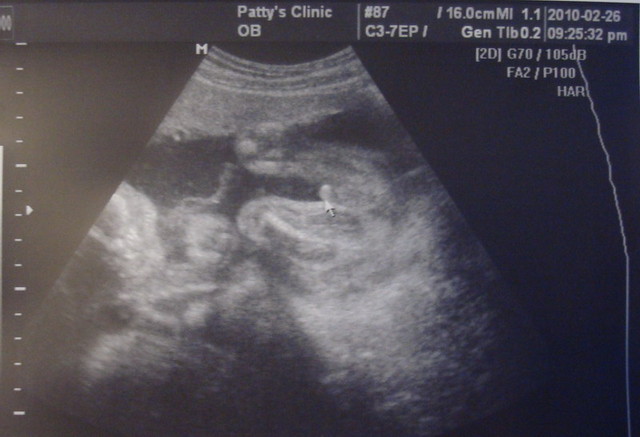

再加上我跟弟妹肚子裡各有一隻小老虎,